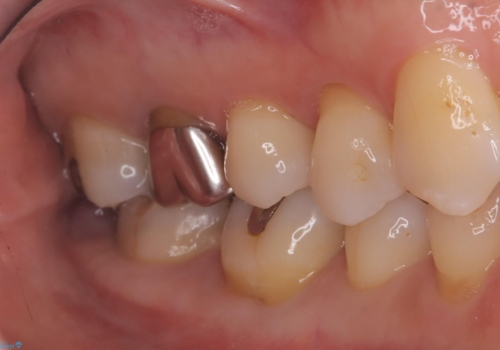

- 主訴:右下6番目と7番目の歯の間に食べかすがしょっちゅう詰まる

コンタクトの再現と歯冠色補綴物へのやり替えを目的とし、セラミックインレーでの治療となりました。

歯間に食渣がつまるのをどうにかしたいとの主訴のもと、治療を開始しました。フロスを通してみると、コンタクトは無く0.25mm程のスペースがありました。

メタルインレーを歯冠色のものに変えたいという希望もあったため、セラミックインレーでのやり替えによるコンタクトの再現をしています。